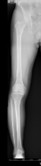

人工膝関節置換術、高位脛骨骨切り術

高位脛骨骨切り術前